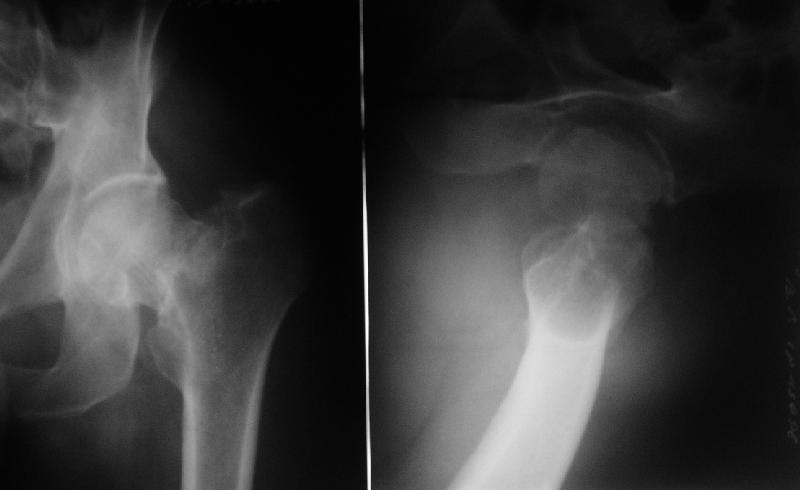

На R-гр. в прямой проекции очень явственно виден малый вертел, что свидетельствует об избыточной наружной ротации бедренной кости. А по тексту следует фиксированная ротация. Возможно, следует провести дополнительное R-обследование.

По снимкам могу предположить, что укорочение составляет ~ 2,0 - 2,5 см и варусная деформация около 7 - 10 градусов. Вероятно, в дальнейшем такое смещение больного может и не беспокоить.

Интересно когда судят о смещении и угле только по р-ме одного сустава. Для этого минимум нужен обзорный снимок таза. Судя по всему здесь Пауэлс 2, гарден2. Судя по клинике перелом стабильный и р-ме. Несмотря на срок после травмы(а это тоже важно) в таком возрасте необходим остеосинтез.Кстати, похожая больная у нас была( тип перелома такой же -3 недели после травмы). Фиксировали V-образными спицами. Перелом через год "как ни странно" сросся. ( а протез установить никогда не поздно). Большой привет!!!!